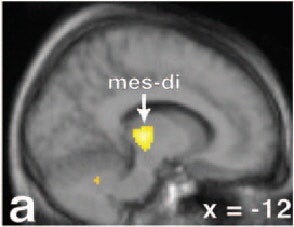

![]() |

| Left, coronal image (d) showing greater bilateral amygdala activations for males versus females for the couples versus neutral stimuli contrast within those regions showing greater activity for males versus females. Couples versus neutral stimuli contrast for males (e), at the same coronal and axial views. The same contrast and views for females (f), showing an absence of differential activity in the ROIs. Figure 2 from Nature Neuroscience, Vol.7, pp. 411 to 416, "Men and women differ in amygdala response to visual sexual stimuli" by Stephan Hamann, Rebecca A Herman, Carla L Nolan, Kim Wallen , et al. |

"Notably, in no region did females show significantly greater activation than males...the greater amygdala activation in males observed here may in part reflect a greater appetitive incentive value of visual sexual stimuli...," Hamann and colleagues noted.